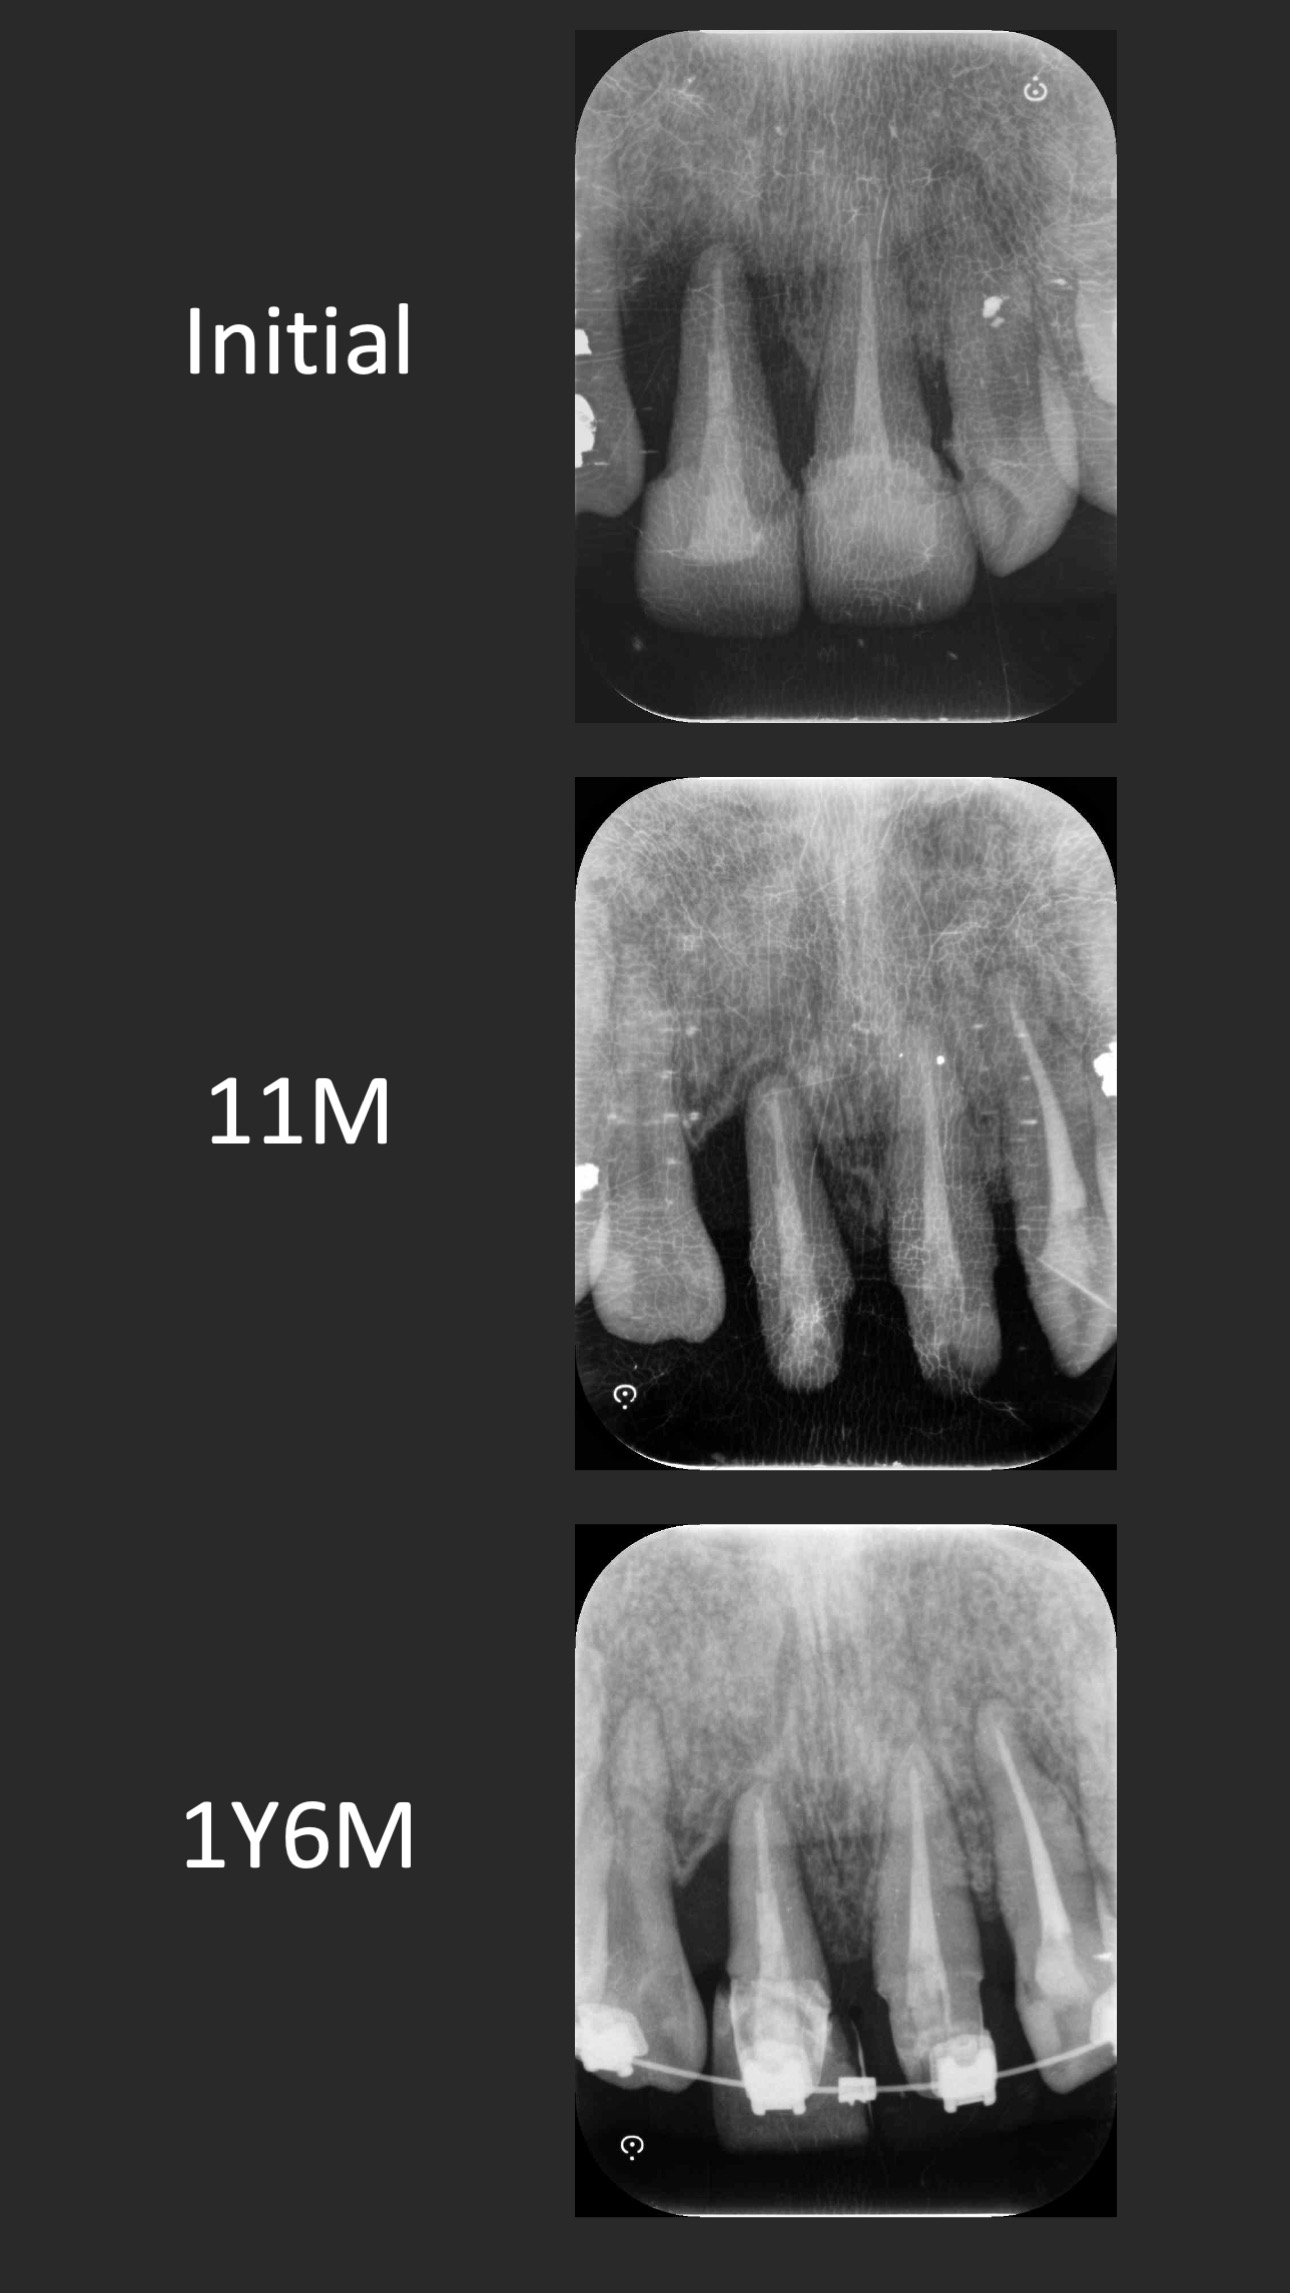

這個案例,最早沒把握能救回來,但是做完非手術治療,發現恢復非常好。

於是大膽地請矯正與假牙專科醫師一起幫忙完成。其實病人本身也同意,若途中狀況不好,還是得拔除。我知道這種案例,其實對其他專科來說,可能是有壓力的,不容易處理,也是難症。

好佳在,兩位神隊友都完成了,非常感謝合作專科的信任,還有,病患六年來維持得非常好,目前囊袋正常、零出血、零發炎。

回頭看,一開始就拔掉牙齒,改走其他路線,或許也可以,每位醫師選擇的或許不一樣,並沒有標準答案。

但是,能幫病患留下自己的牙齒,真的是很開心的一件事~~